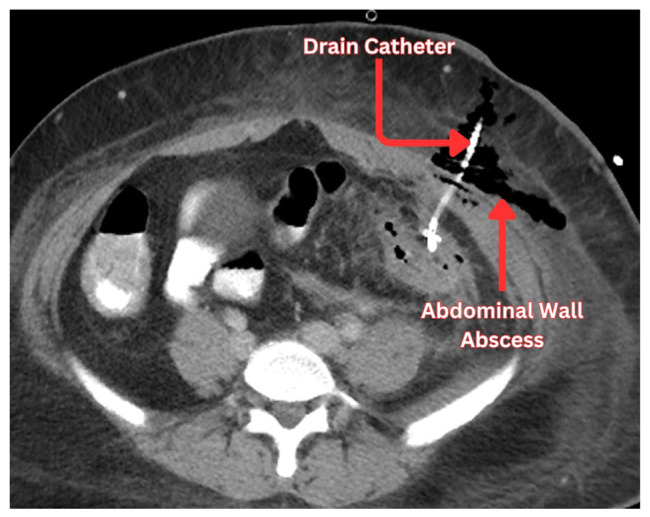

憩室囊的炎症称为急性憩室炎,有时可导致脓肿形成。经皮引流是治疗憩室脓肿的常规方法。作为一种用于从脓肿中清除大量感染液体的微创手术,经皮引流术成为一种有吸引力的选择。从历史上看,手术切除脓肿导致多次住院治疗,增加了医疗资源的负担。随着放射学技术的进步,ct引导下经皮引流憩室脓肿确保了患者满意度的提高和医疗成本的降低。选择手术或经皮引流憩室脓肿仍然是一个问题的争论医师。经皮引流手术的结果在文献中是分散的。在憩室脓肿的治疗过程中,熟悉经皮引流或结肠切除术的选择标准是很重要的。经皮引流可以防止紧急结肠切除术,但它并不总是一个无风险的程序。可引起持续性脓肿、新发脓肿、腹壁脓肿、腹膜炎等并发症。因此,医生必须提前做好准备,通过选择合适的人群进行手术,并确保良好的导管护理,包括重新调整导管,冲洗导管和升级导管尺寸,以预防这些并发症。医生不仅要预防这些并发症,还要有效地治疗它们。本文旨在从临床角度总结经皮引流憩室脓肿的重要结果及其进一步处理。

The inflammation of the diverticular pouch is called acute diverticulitis which can result in abscess formations sometimes. Percutaneous drainage is routinely considered for the management of diverticular abscesses. Being a minimally invasive procedure employed for the removal of large collections of infected fluid from the abscesses, percutaneous drainage emerged as an appealing option. Historically, surgical removal of the abscesses has resulted in multiple hospitalizations and an increased burden on healthcare resources. With the advancement in radiological techniques, CT-guided percutaneous drainage of diverticular abscesses ensured enhanced patient satisfaction and reduced healthcare costs. The choice between surgery or percutaneous drainage of diverticular abscess remains a matter of debate among physicians. The outcomes of percutaneous drainage procedures are scattered across the literature. It is important to be familiar with the criteria regarding the choice of percutaneous drainage or colectomy during the management of diverticular abscesses. Percutaneous drainage can prevent emergent colectomy but it is not always a risk-free procedure. It can bring complications including persistent abscess, new onset abscess, abdominal wall abscess, and peritonitis. Therefore, a physician must prepare in advance to prevent these complications by selecting the right population for the procedure and ensuring good catheter care which involves readjusting the catheter, flushing the catheter and upgrading the size of the catheter. A physician not only prevents these complications but also effectively treats them. This review paper aims to summarize the important outcomes of percutaneous drainage of diverticular abscesses and their further management from a clinical standpoint.